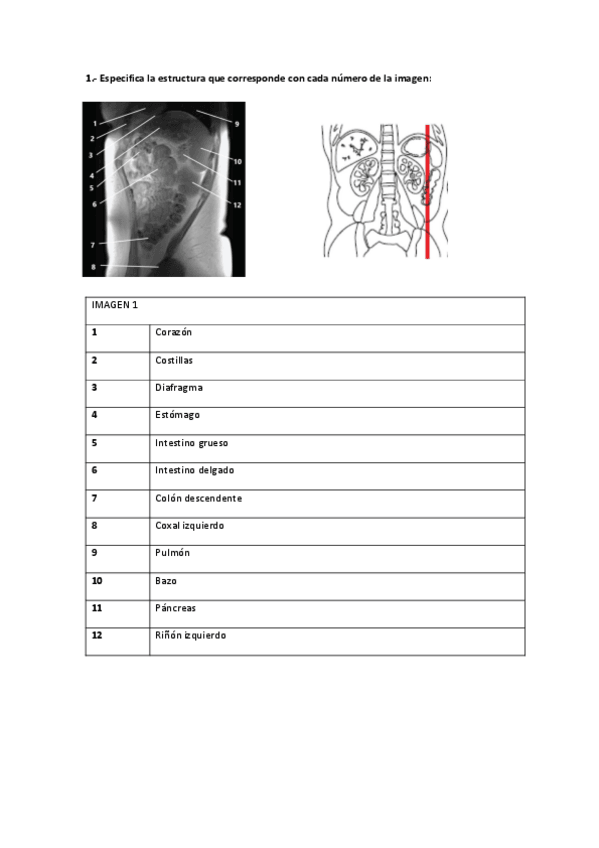

ACTIVIDADES EVALUABLES

He publicado nuevos apuntes de Anatomía por la imagen: ACTIVIDADES EVALUABLES

ACTIVIDADES ANATOMÍA

He publicado nuevos apuntes de Anatomía por la imagen: ACTIVIDADES ANATOMÍA